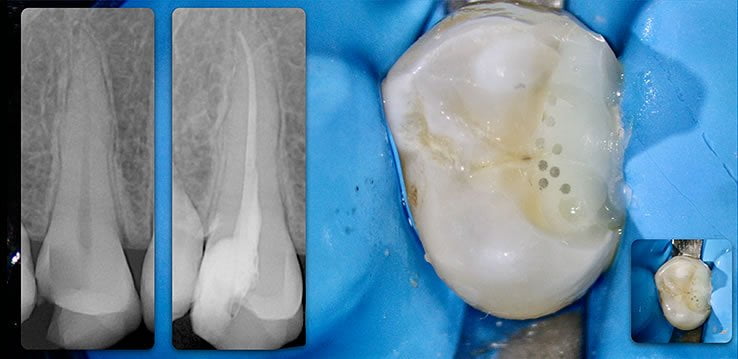

Template for x-rays

Biolight® DRILL-FREE posts are available in bundles of 4, 6, 9 and 12 strands. The post size is selected based on the width of the canal at the coronal area. Depending upon the canal width at the apical stop, a certain number of strands must be pushed to the stop. Both of the measurements are made with the assistance of a radiograph and the template that is included in the TRAINING KIT.